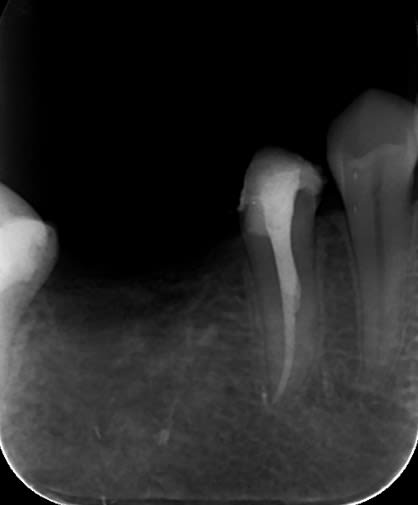

On va encore me traiter de chieur mais t'es a 2 mm de l'apex de la 47 en distal, bonne chance pour démonter un truc comme ça pour faire le RTE si problème...

Je ne pense pas être à 2 mm de l'apex radiologique. Par contre je suis à l'apex détecté par le localisateur. Je reprendrais d'autres rétro sous différents angle pour voir...

> bonne chance pour démonter un truc comme ça pour faire le RTE si problème...

Tu coupes le bridge au niveau de l'inter, et tu te retrouves avec :

- une endocouronne sur 47 avec à peine 1 mm de hauteur coronaire en distal ;

- une couronne Richmond sur 45